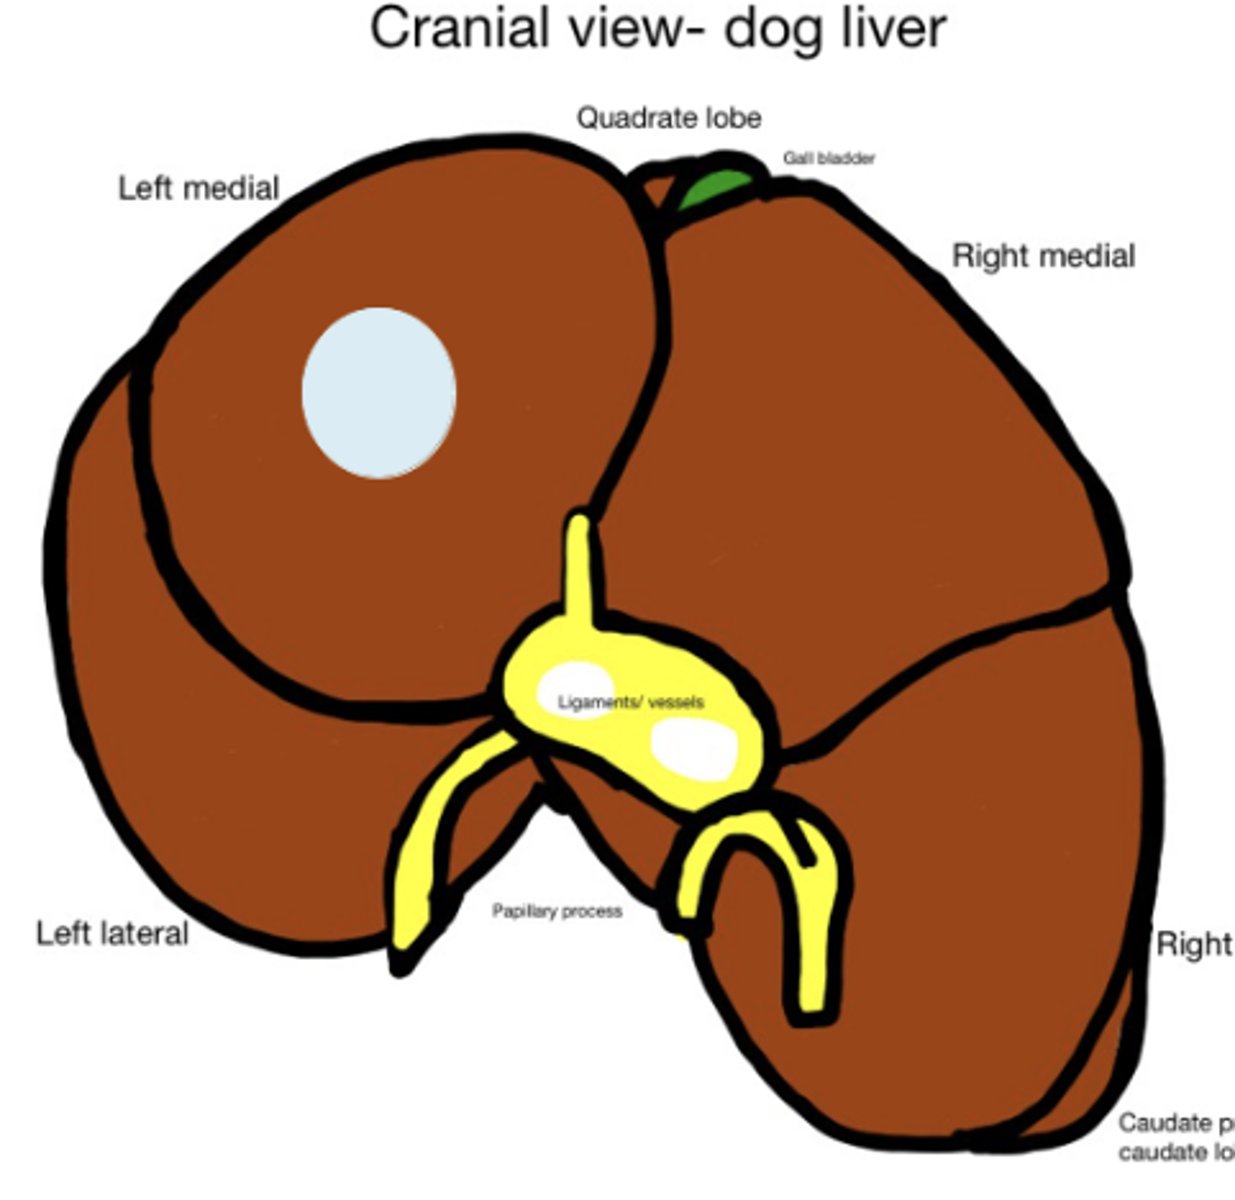

Cirrhosis caused by long term exposure to toxic substances

What has caused this gross appearance of this dog liver